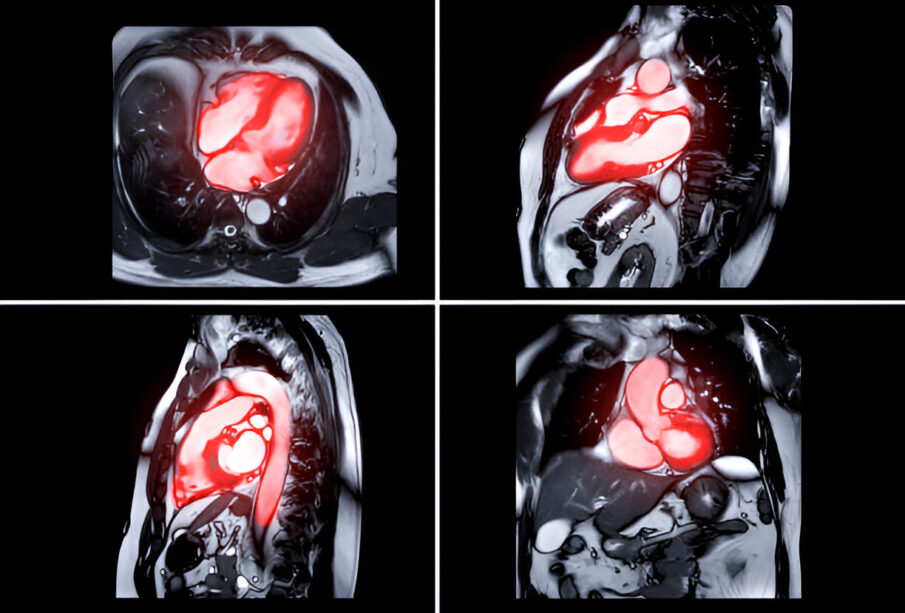

Η στένωση της αορτής ή η ανεπάρκεια της αορτής εμφανίζονται όταν η βαλβίδα της αορτής δεν ανοίγει ή δεν κλείνει πλήρως, με αποτέλεσμα να περιορίζεται η ροή αίματος από την αριστερή κοιλία προς την αορτή και τελικά στον οργανισμό, ή να επιστρέφει το αίμα προς την αριστερή κοιλία. Η αορτική βαλβίδα βρίσκεται ανάμεσα στην αριστερή κοιλία και την αορτή, που αποτελεί τη μεγαλύτερη αρτηρία του σώματος. Ο βασικός ρόλος της βαλβίδας είναι να ανοιγοκλείνει, ρυθμίζοντας έτσι τη διέλευση του οξυγονωμένου αίματος από την αριστερή κοιλία στην αορτή, προκειμένου να διανεμηθεί σε όλα τα όργανα και στις στεφανιαίες αρτηρίες.